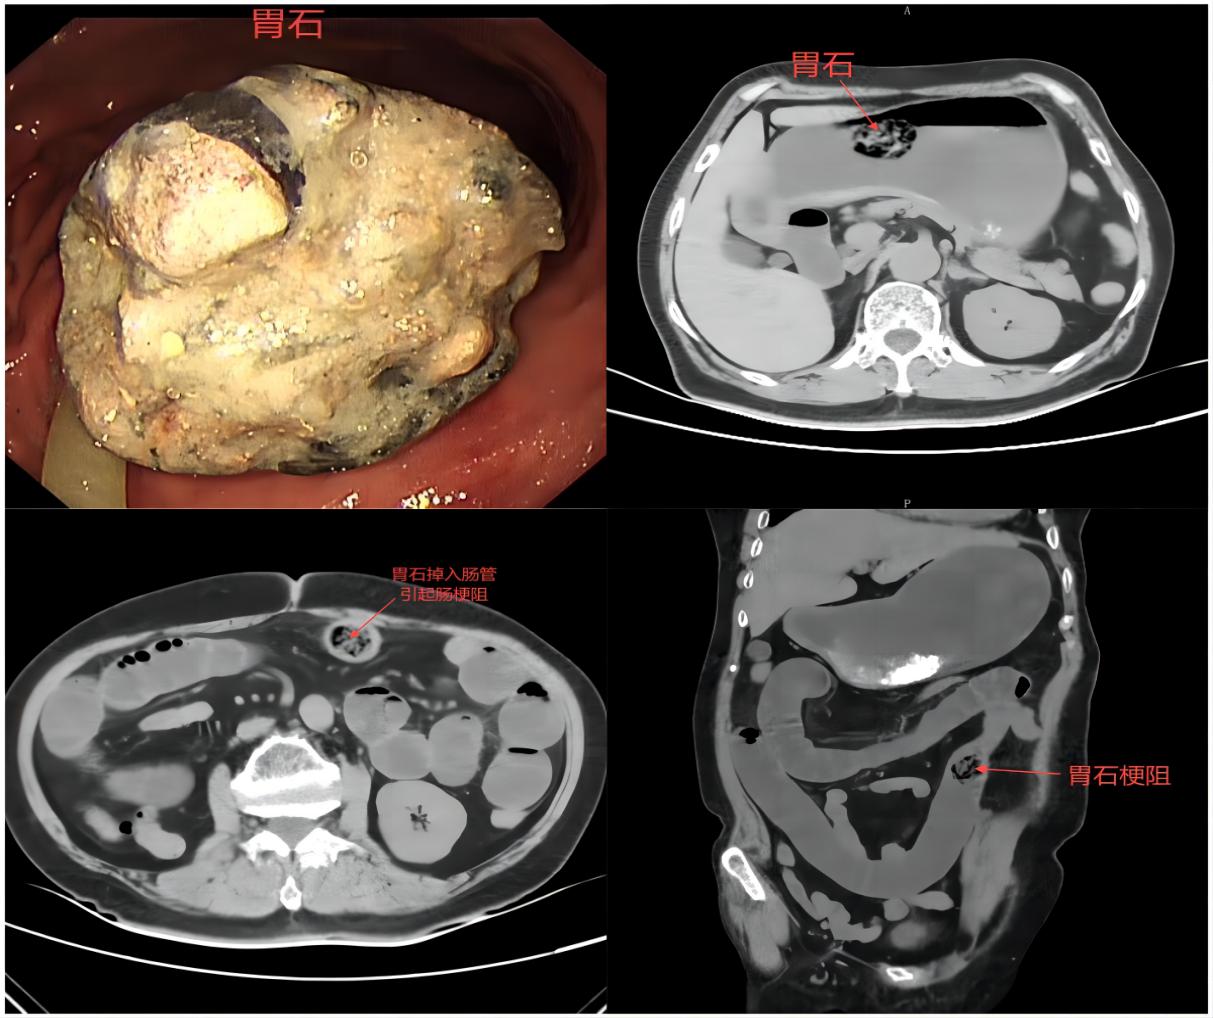

胃石,顾名思义,是指发生在胃部的结石。柿子中含有较多的鞣酸,这些鞣酸在胃酸的作用下容易与食物中的蛋白质结合,形成不溶于水的沉淀物,当这些沉淀物在胃内逐渐聚集、增大时,便会形成胃石。胃石会阻碍胃的正常蠕动,引起胃痛、胃胀、恶心、呕吐等症状,甚至可能导致消化道梗阻、溃疡等严重后果。